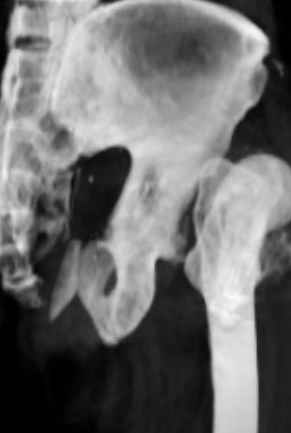

Уважаемые коллеги,Мужчина 1952 г.р. поступил в 36 больницу Екатеринбурга 1 июня 2004 г. Диагноз: Множественный перелом ребер слева, субтотальный гемоторакс, оскольчатый перелом шейки правого бедра.Повреждение таза не диагностировано. 17 июня 2004 г. - открытый остеосинтеза шейки бедра винтами с костной аутопластикой. Заживление раны первичное. Выписан 1 июля. 4 июля отметил укорочение конечности. При контрольном осмотре через 1 месяц после остеосинтеза - передний вывих бедра. Неправильно срастающийся перелом костей таза.Вопрос - особенности эндопртезирования тазобедренного сустава в этой ситуации?

Перелом там от бокового сжания, похоже на LC-I, т.е. компрессионный перелом крестца и на этой же стороне лонной и седалищной. Впадина выглядит совершенно целой. Если там и есть какая-то импрессия в переднем отделе - то микроскопическая.

По видимому снимки н/к сделаны в положении наружной ротации 90гр. И если даже так, то можно определить, что после выполненного остеосинтеза, шейка бедра практически отсутствует.

Даже при нормальной, не поврежденной впадине такое расположение головки относительно большого вертела обречено на вывих (теоретическое или биомеханическое обоснование можно найти в работах Рагозина А.О.).